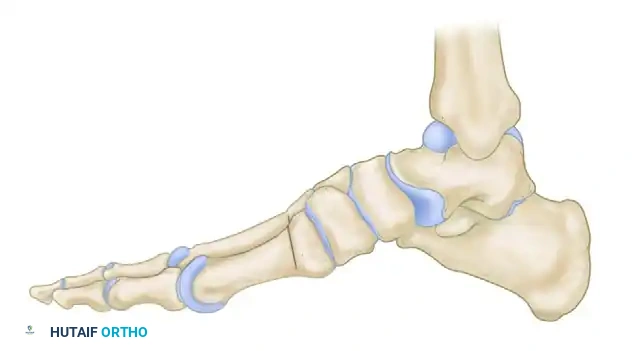

Preoperative lateral skeletal representation demonstrating severe forefoot equinus, elevated longitudinal arch, and cavus deformity typical of advanced Charcot-Marie-Tooth disease.